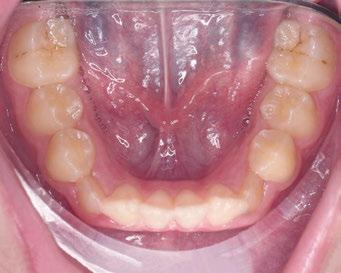

La respiración bucal es muy frecuente en niños con asma y surge como una función adaptativa, ya que tienen dificultad respiratoria. Puede implicar cambios de postura a nivel cervical, afectando al crecimiento del niño; además de alteraciones en el crecimiento de maxilares y en los m ú sculos orofaciales, la posición baja de la lengua detiene el crecimiento transversal, originando paladar ojival y mordida cruzada posterior. A nivel anterior, la alteración en la posición lingual provoca deglución atípica.

Castañeda-Zetina y cols. realizaron un estudio para comparar las maloclusiones en niños asmáticos y sanos, en el cual se incluyeron 186 pacientes de entre 5 y 12 años. Los resultados obtenidos fueron que más del 50% de los niños asmáticos tienen respiración oral. Las principales alteraciones oclusales presentadas eran mordida abierta anterior y mordida cruzada posterior, menos frecuente; además de una menor frecuencia de clase III, solo un 11,6%, ya que el cambio postural de estos pacientes favorece la entrada del aire inclinando la cabeza hacia atrás y favoreciendo la aparición de clase II al posterorrotar la mandíbula. Estas modificaciones posturales van a producir alteraciones maxilares y desequilibrio en los m ú sculos periorales; por ello, su detección precoz ayudará a resolver el problema con un abordaje multidisciplinario y dando armonía al complejo dentoesquelético (56).